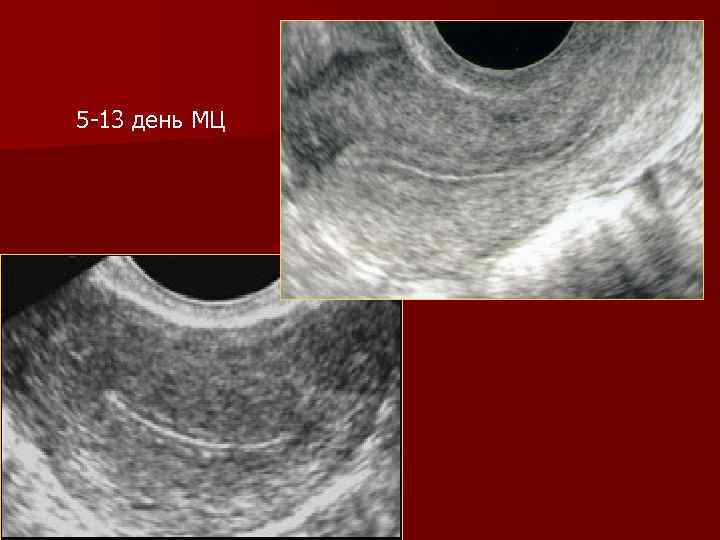

5 -13 день МЦ